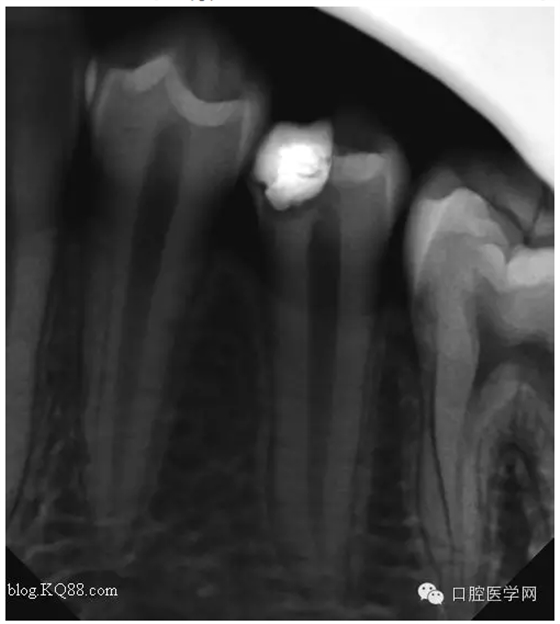

最后的充填我是這樣做的:去除部分暫封物。直接樹(shù)脂充填。